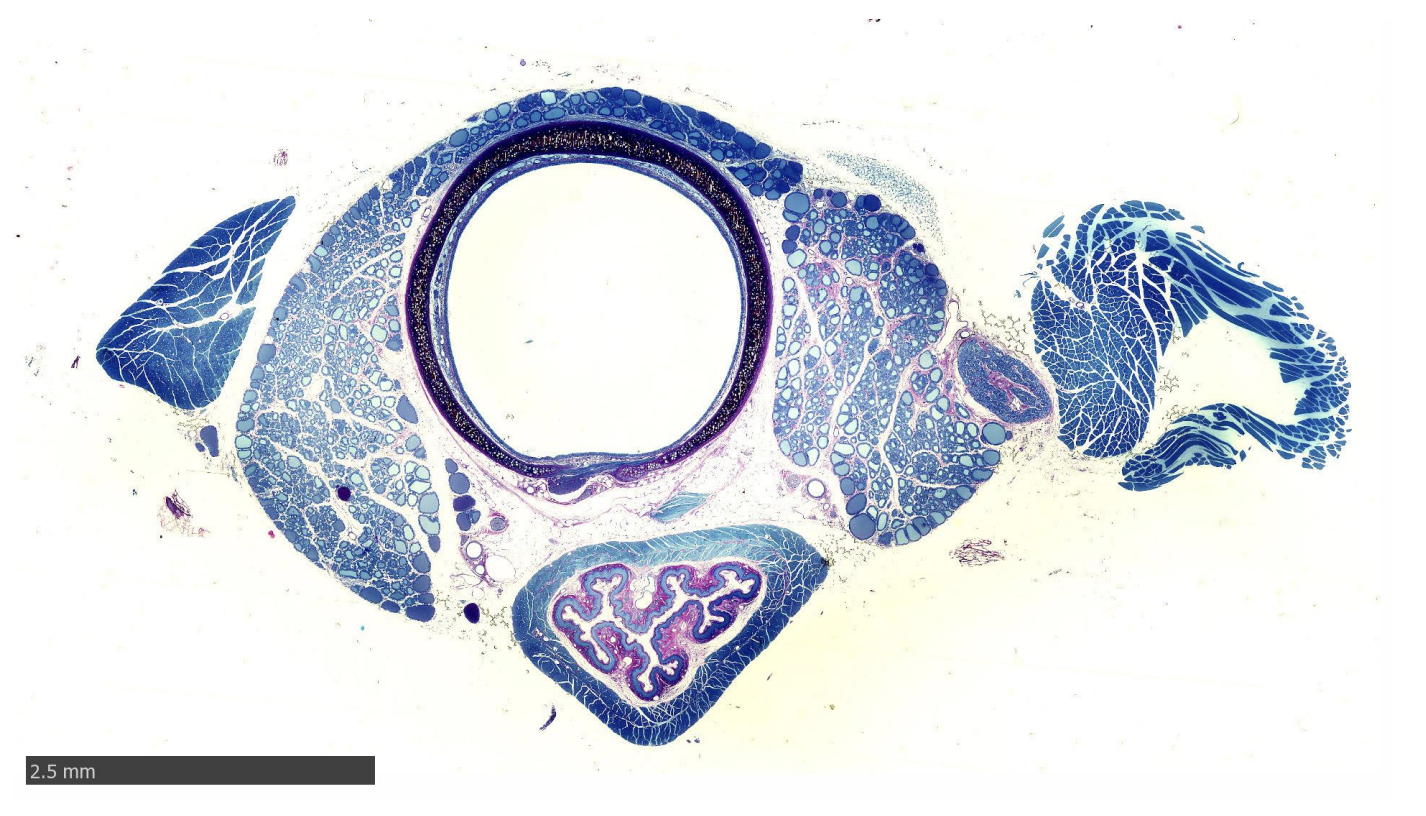

Oesophagus and Trachea of rat

collagen?